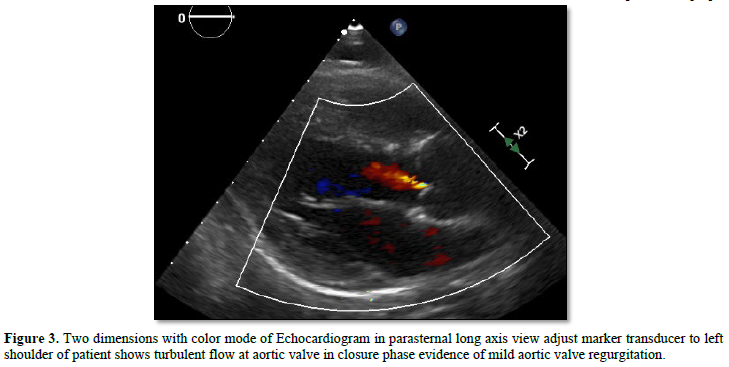

The outflow tract and semilunar valve function both aortic and pulmonic valves used the parasternal long axis view (Figure 2) and modified parasternal long axis view with anterior angulation of transducer. Because of aortic root dilated and valve regurgitation was common occur approximately 22% in ten years follow up [15]. The parasternal short axis view was a limitation for demonstrating both semilunar valve in same view (Figures 2 & 3). The overriding aorta may be considering the cause of obstruction the outflow tract after closure septal defect [16].